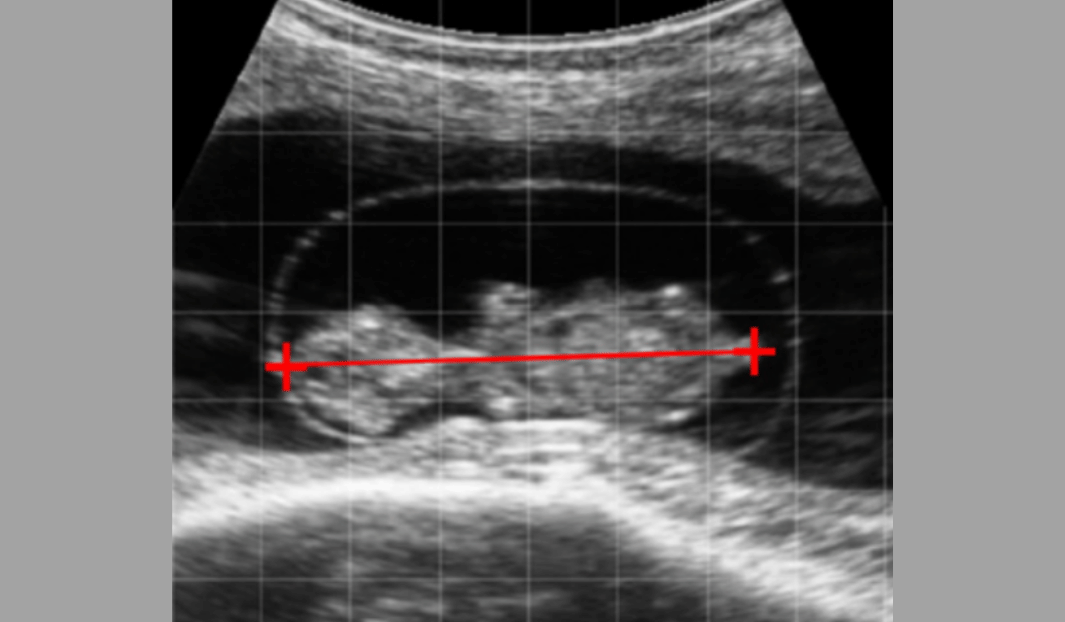

The scanner is purpose-built for fertility examinations and has non-reproductive applications.

~ definition: veterinary ultrasound

– uses high-frequency sound waves (1.5 – 15 MHz) to create images of an animal’s body structures.

A transducer probe directs sound into the body and receives echoes that bounce back off organs and tissues.

Echo patterns are sent electronically to the machine’s computer and converted into images.

It is a non-invasive technique.